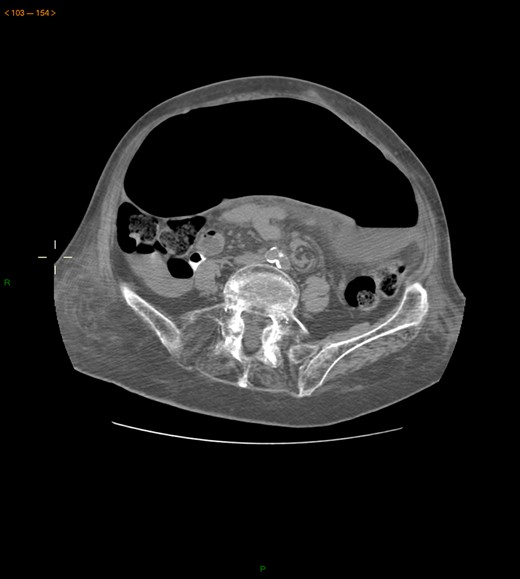

Case 2: A 92-year-old women, without previous abdominal surgery or history of abdominal trauma or peritoneal infections was admitted to the emergency department with generalized abdominal pain. Physical exam revealed markedly distended abdomen with generalized abdominal pain with tenderness. Laboratory investigation on admission: white cell count of 30.200/mm3 with 84.7% neutrophils, protein C reactive of 13.6 mg/dL and lactates of 2.17 mmol/l. Abdominal X-ray showed a marked colonic enlargement. Abdominal-pelvic CT identified a colonic volvulus associated with a transmesocolic hernia with transmural necrosis of the colon sigmoid (Figs 2 and 3). The patient was proposed to laparotomy during which a volvulus of colon sigmoid with transmural necrosis in a strangulated transverse transmesocolic and transomental (great omentum) hernia was identified (Figs 4 and 5). A Hartmann procedure was conducted and the patient was discharged at fifth post-operative day. At 3 months follow-up consultation, the patient remained free of complains.

Abdominal-pelvic CT—coronal plane: colonic volvulus associated with a transmesocolic hernia with transmural necrosis of the colon sigmoid.